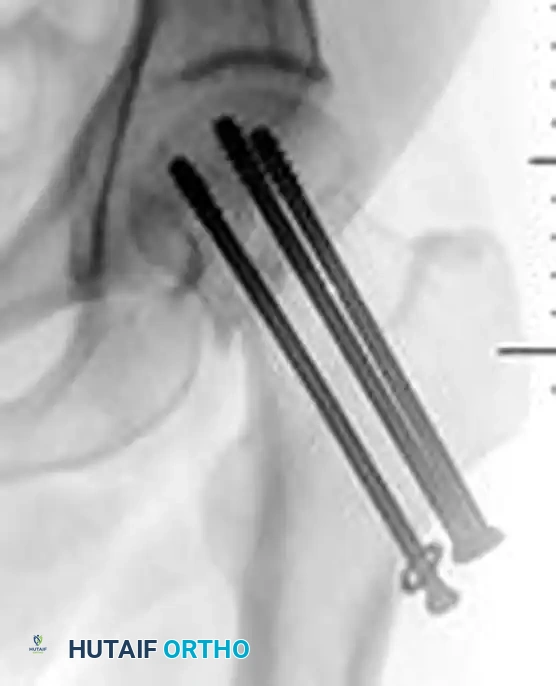

Figure 55-15A: Intraoperative fluoroscopic anteroposterior view demonstrating the initial fixation of a minimally displaced femoral neck fracture utilizing three partially threaded cannulated screws.

- Fully Threaded Screws: In an attempt to minimize femoral neck shortening, a partially threaded screw used for compression can be exchanged for, or augmented with, a fully threaded screw. Fully threaded screws act as position screws, maintaining length and preventing further collapse once initial compression is achieved.